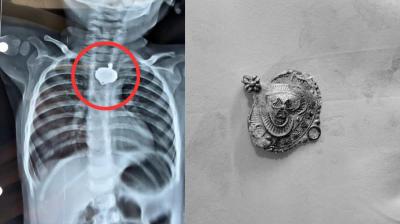

जिला कोर्ट का बड़ा फैसला: इंदौर में भ्रूण लिंग परीक्षण के 14 साल पुराने मामले में दो डॉक्टरों को एक-एक साल की सजा और जुर्माना

इंदौरः मध्य प्रदेश के इंदौर की जिला अदालत ने 14 साल पुराने एक मामले में बड़ा फैसला सुनाया है। कोर्ट ने दो डॉक्टरों को एक-एक साल के सश्रम कारावास की...